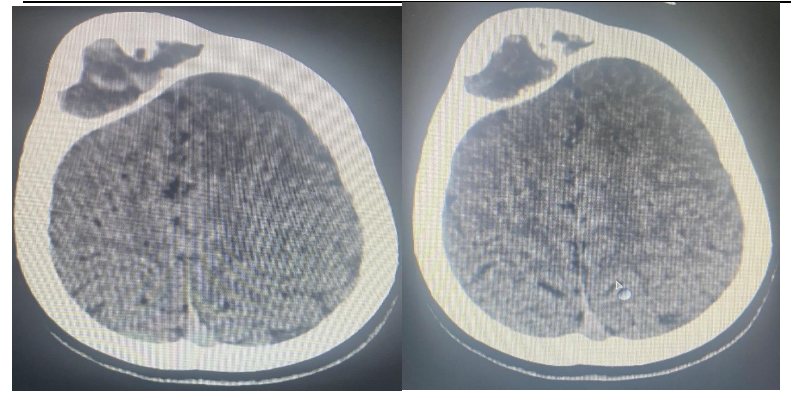

Fig 2 A and B : Head CT: Showed: expansile lytic lesion seen in  the right frontal bone ,This lesion shows ground glass appearance .The diploic space is widened with displacement of  the outer  table .It measures 50x28 mm and no fracture seen. It causes mass effect on the frontal lobe. There is no periosteal reaction